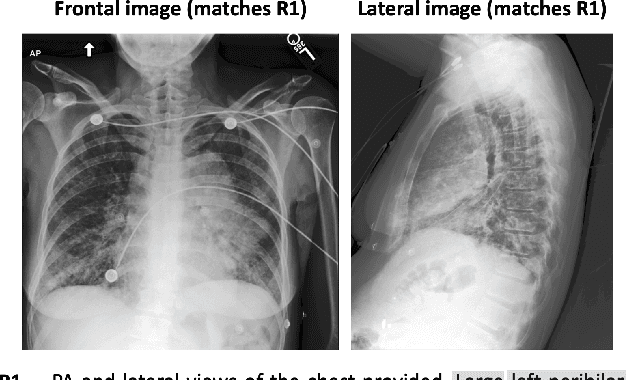

Abstract:The paper proposes a novel evaluation metric for automatic medical report generation from X-ray images, VLScore. It aims to overcome the limitations of existing evaluation methods, which either focus solely on textual similarities, ignoring clinical aspects, or concentrate only on a single clinical aspect, the pathology, neglecting all other factors. The key idea of our metric is to measure the similarity between radiology reports while considering the corresponding image. We demonstrate the benefit of our metric through evaluation on a dataset where radiologists marked errors in pairs of reports, showing notable alignment with radiologists' judgments. In addition, we provide a new dataset for evaluating metrics. This dataset includes well-designed perturbations that distinguish between significant modifications (e.g., removal of a diagnosis) and insignificant ones. It highlights the weaknesses in current evaluation metrics and provides a clear framework for analysis.

Abstract:Generating medical reports for X-ray images is a challenging task, particularly in an unpaired scenario where paired image-report data is unavailable for training. To address this challenge, we propose a novel model that leverages the available information in two distinct datasets, one comprising reports and the other consisting of images. The core idea of our model revolves around the notion that combining auto-encoding report generation with multi-modal (report-image) alignment can offer a solution. However, the challenge persists regarding how to achieve this alignment when pair correspondence is absent. Our proposed solution involves the use of auxiliary tasks, particularly contrastive learning and classification, to position related images and reports in close proximity to each other. This approach differs from previous methods that rely on pre-processing steps using external information stored in a knowledge graph. Our model, named MedRAT, surpasses previous state-of-the-art methods, demonstrating the feasibility of generating comprehensive medical reports without the need for paired data or external tools.

Abstract:Generating medical reports for X-ray images presents a significant challenge, particularly in unpaired scenarios where access to paired image-report data for training is unavailable. Previous works have typically learned a joint embedding space for images and reports, necessitating a specific labeling schema for both. We introduce an innovative approach that eliminates the need for consistent labeling schemas, thereby enhancing data accessibility and enabling the use of incompatible datasets. This approach is based on cycle-consistent mapping functions that transform image embeddings into report embeddings, coupled with report auto-encoding for medical report generation. Our model and objectives consider intricate local details and the overarching semantic context within images and reports. This approach facilitates the learning of effective mapping functions, resulting in the generation of coherent reports. It outperforms state-of-the-art results in unpaired chest X-ray report generation, demonstrating improvements in both language and clinical metrics.

Abstract:Medical imaging analysis plays a critical role in the diagnosis and treatment of various medical conditions. This paper focuses on chest X-ray images and their corresponding radiological reports. It presents a new model that learns a joint X-ray image & report representation. The model is based on a novel alignment scheme between the visual data and the text, which takes into account both local and global information. Furthermore, the model integrates domain-specific information of two types -- lateral images and the consistent visual structure of chest images. Our representation is shown to benefit three types of retrieval tasks: text-image retrieval, class-based retrieval, and phrase-grounding.